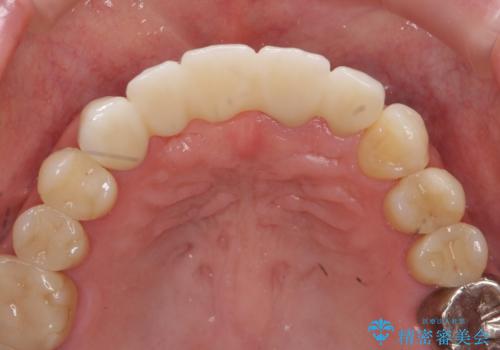

前歯が折れた 前歯部審美セラミックブリッジ治療

- 57万円(仮歯・ファイバーコア・ジルコニアクラウン×5)費用は治療当時の料金となります

かみ合わせの観点からインプラント治療は難しく、入れ歯も希望されなかったためブリッジによる補綴を選択しました。